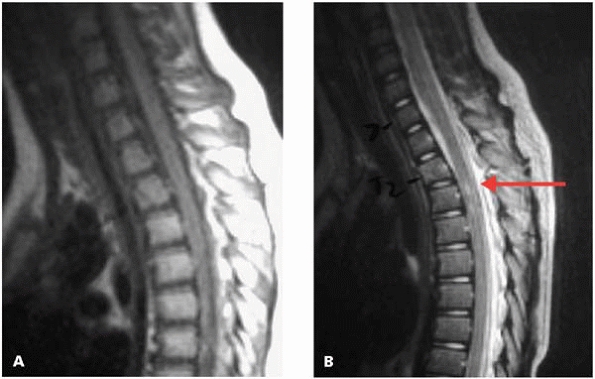

![]() |

|

▪ FIGURE 4-16 This 3 year old presented after a fall with a minor concussion. The radiographs, including the lateral (A) and full flexion lateral (B)

were read as normal by a very capable and respected pediatric radiologist. No further imaging was performed. The boy was lost to followup, then returned nearly 2 years later because of intermittent neck pain. The lateral (C) shows an odontoid nonunion, read as “os odontoidium.” The nonunion is clearly visualized on the MRI (D). The lesson? Even in the best of hands, some cervical spine injuries in young children cannot be detected on plain radiographs. Use MRI or CT if there is concern for an occult injury. |

▪ FIGURE 4-17

SICWORA. This patient came into the ED with no neurologic deficits. Initial plain radiographs were read as normal. Paraplegia developed the next morning. MRI (A, B) increased 2 vertebral fractures and signal in the spinal cord, confirming injury (red arrow). |